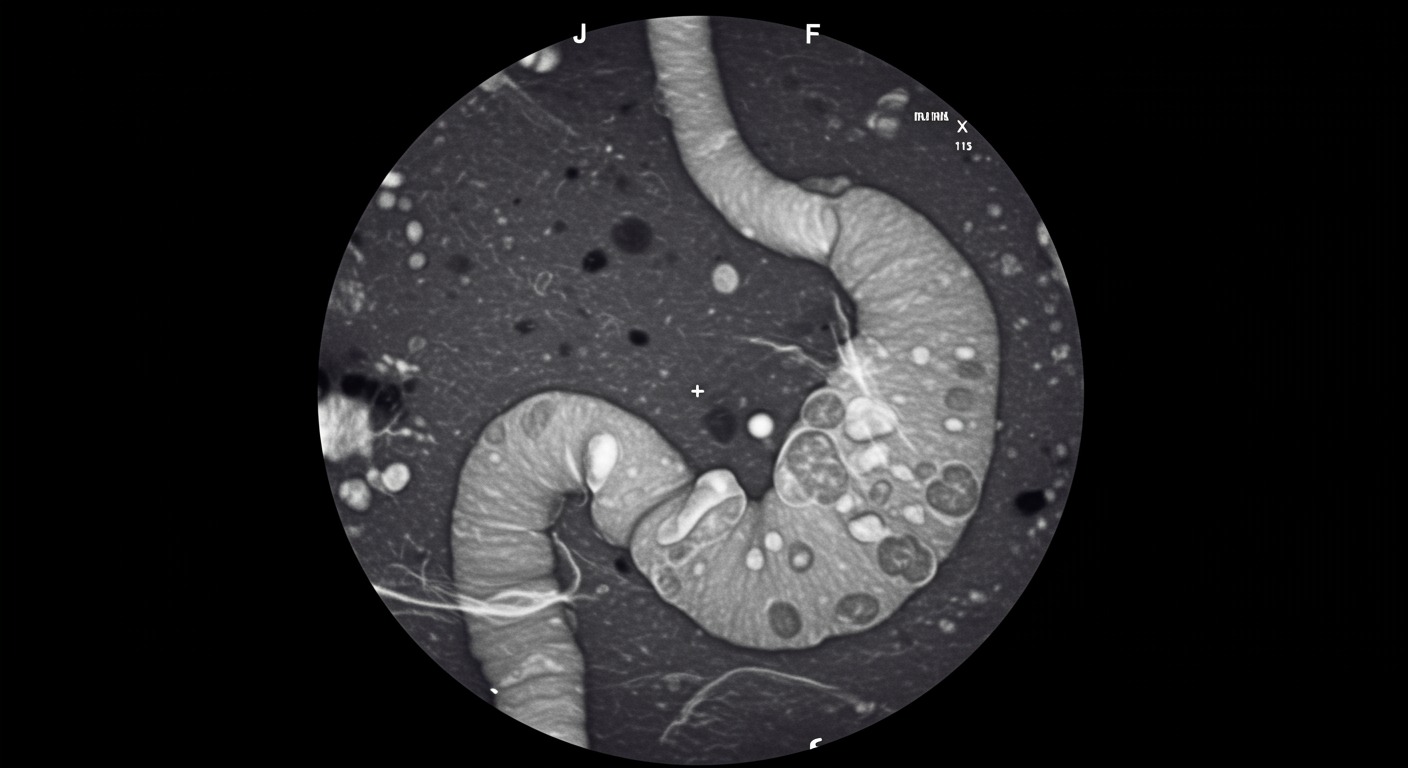

This case series documented two patients with large PPI-induced gastric polyps (>2 cm) who achieved complete polyp regression within 2 months of proton pump inhibitor discontinuation. The cases included detailed endoscopic documentation and histological analysis to confirm both the PPI-induced nature of the polyps and their complete resolution.

The research demonstrates that even large, concerning-appearing polyps can undergo rapid and complete regression when the underlying hypergastrinemia is addressed through PPI cessation.

- Complete regression time: 100% polyp resolution within 2 months of PPI discontinuation

- Polyp size: Both cases involved polyps >2 cm in diameter

- Regression rate: Complete disappearance rather than partial reduction

- Endoscopic confirmation: Serial endoscopy documented complete resolution

- Histological findings: Confirmed hyperplastic nature without dysplasia